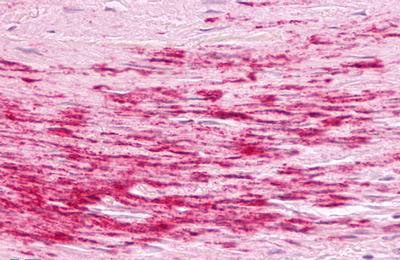

(Anti-B1R / BDKRB1 antibody IHC of human artery, smooth muscle, atherosclerosis. Immunohistochemistry of formalin-fixed, paraffin-embedded tissue after heat-induced antigen retrieval. Antibody dilution 5 ug/ml.)